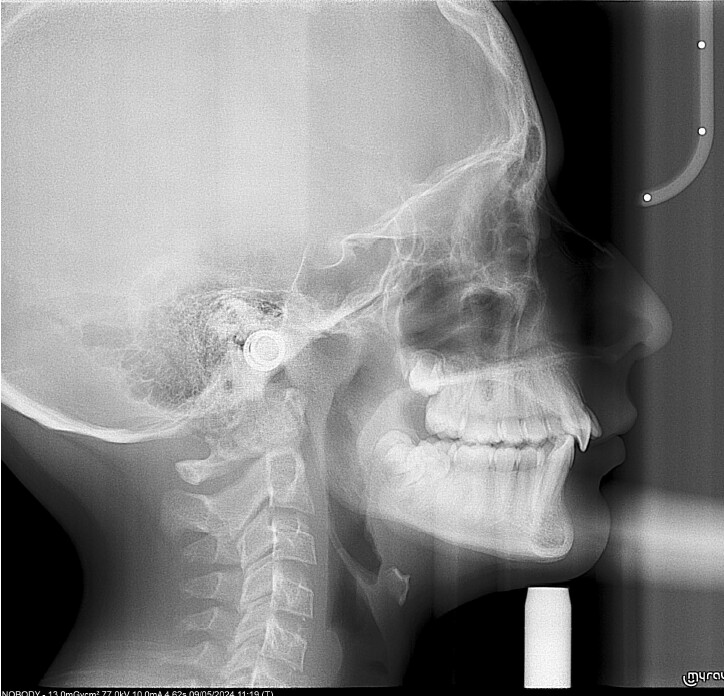

A 13-year-old male patient presented with a deep bite, characterized by near-complete coverage of the mandibular incisors. Clinical evaluation revealed bi-arch crowding, dental rotations, and proclination of the maxillary lateral incisors, contributing to the patient’s esthetic concerns. The facial profile was retrusive, consistent with mandibular retrognathism, and no significant periodontal abnormalities were detected.

The patient presented with a skeletal Class II relationship with bilateral molar and canine Class II and a Class II division 2 dental pattern. The deep bite was associated with anteroinferior crowding and an accentuated Curve of Spee. Facial analysis revealed good symmetry, a slightly increased lower facial third, and a convex profile characterized by mandibular and chin retrusion. Lip competence was mildly reduced, with a decreased nasolabial angle and mentalis hyperactivity, all of which compromised overall facial harmony.

The treatment was carried out using Angel Aligner clear aligners, with strict adherence to periodontal biological limits. Both maxillary incisor intrusion and transverse expansion were carefully monitored throughout the process to prevent any periodontal compromise. Mandibular advancement was initiated directly from the 4th aligner using advancement blocks, eliminating the need for a preliminary pre-advancement phase. The patient was at the CS3 stage of cervical vertebral maturation, corresponding to the pubertal growth spurt, a biologically favorable period for condylar remodeling and skeletal adaptation. A total of 35 aligners with advancement blocks were used, followed by 10 additional aligners incorporating Class II elastics on Angel Buttons to finalize rotations and alignment. With weekly aligner changes, the overall treatment duration was approximately 45 weeks (10 months), aligning with the expected biological timeline for condylar remodeling. For mandibular anterior intrusion, the Frog Protocol combined with interproximal reduction (IPR) achieved complete leveling of the Curve of Spee.